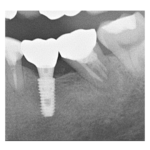

―症例集―

症例一覧